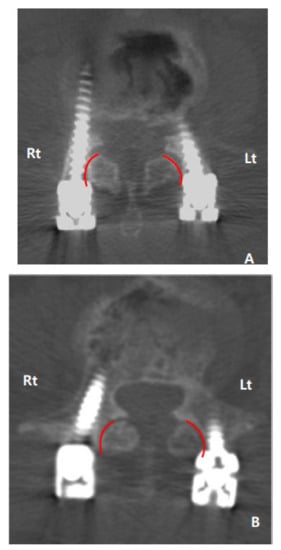

| Type (Score) | ASP Group (112 Screws) | Non-ASP Group (62 Screws) |

| I (0) | 59 screws (52.7%) | 43 screws (69.4%) |

| II (1) | 26 screws (23.2%) | 14 screws (22.6%) |

| III (2) | 27 screws (24.1%) | 5 screws (8.0%) |